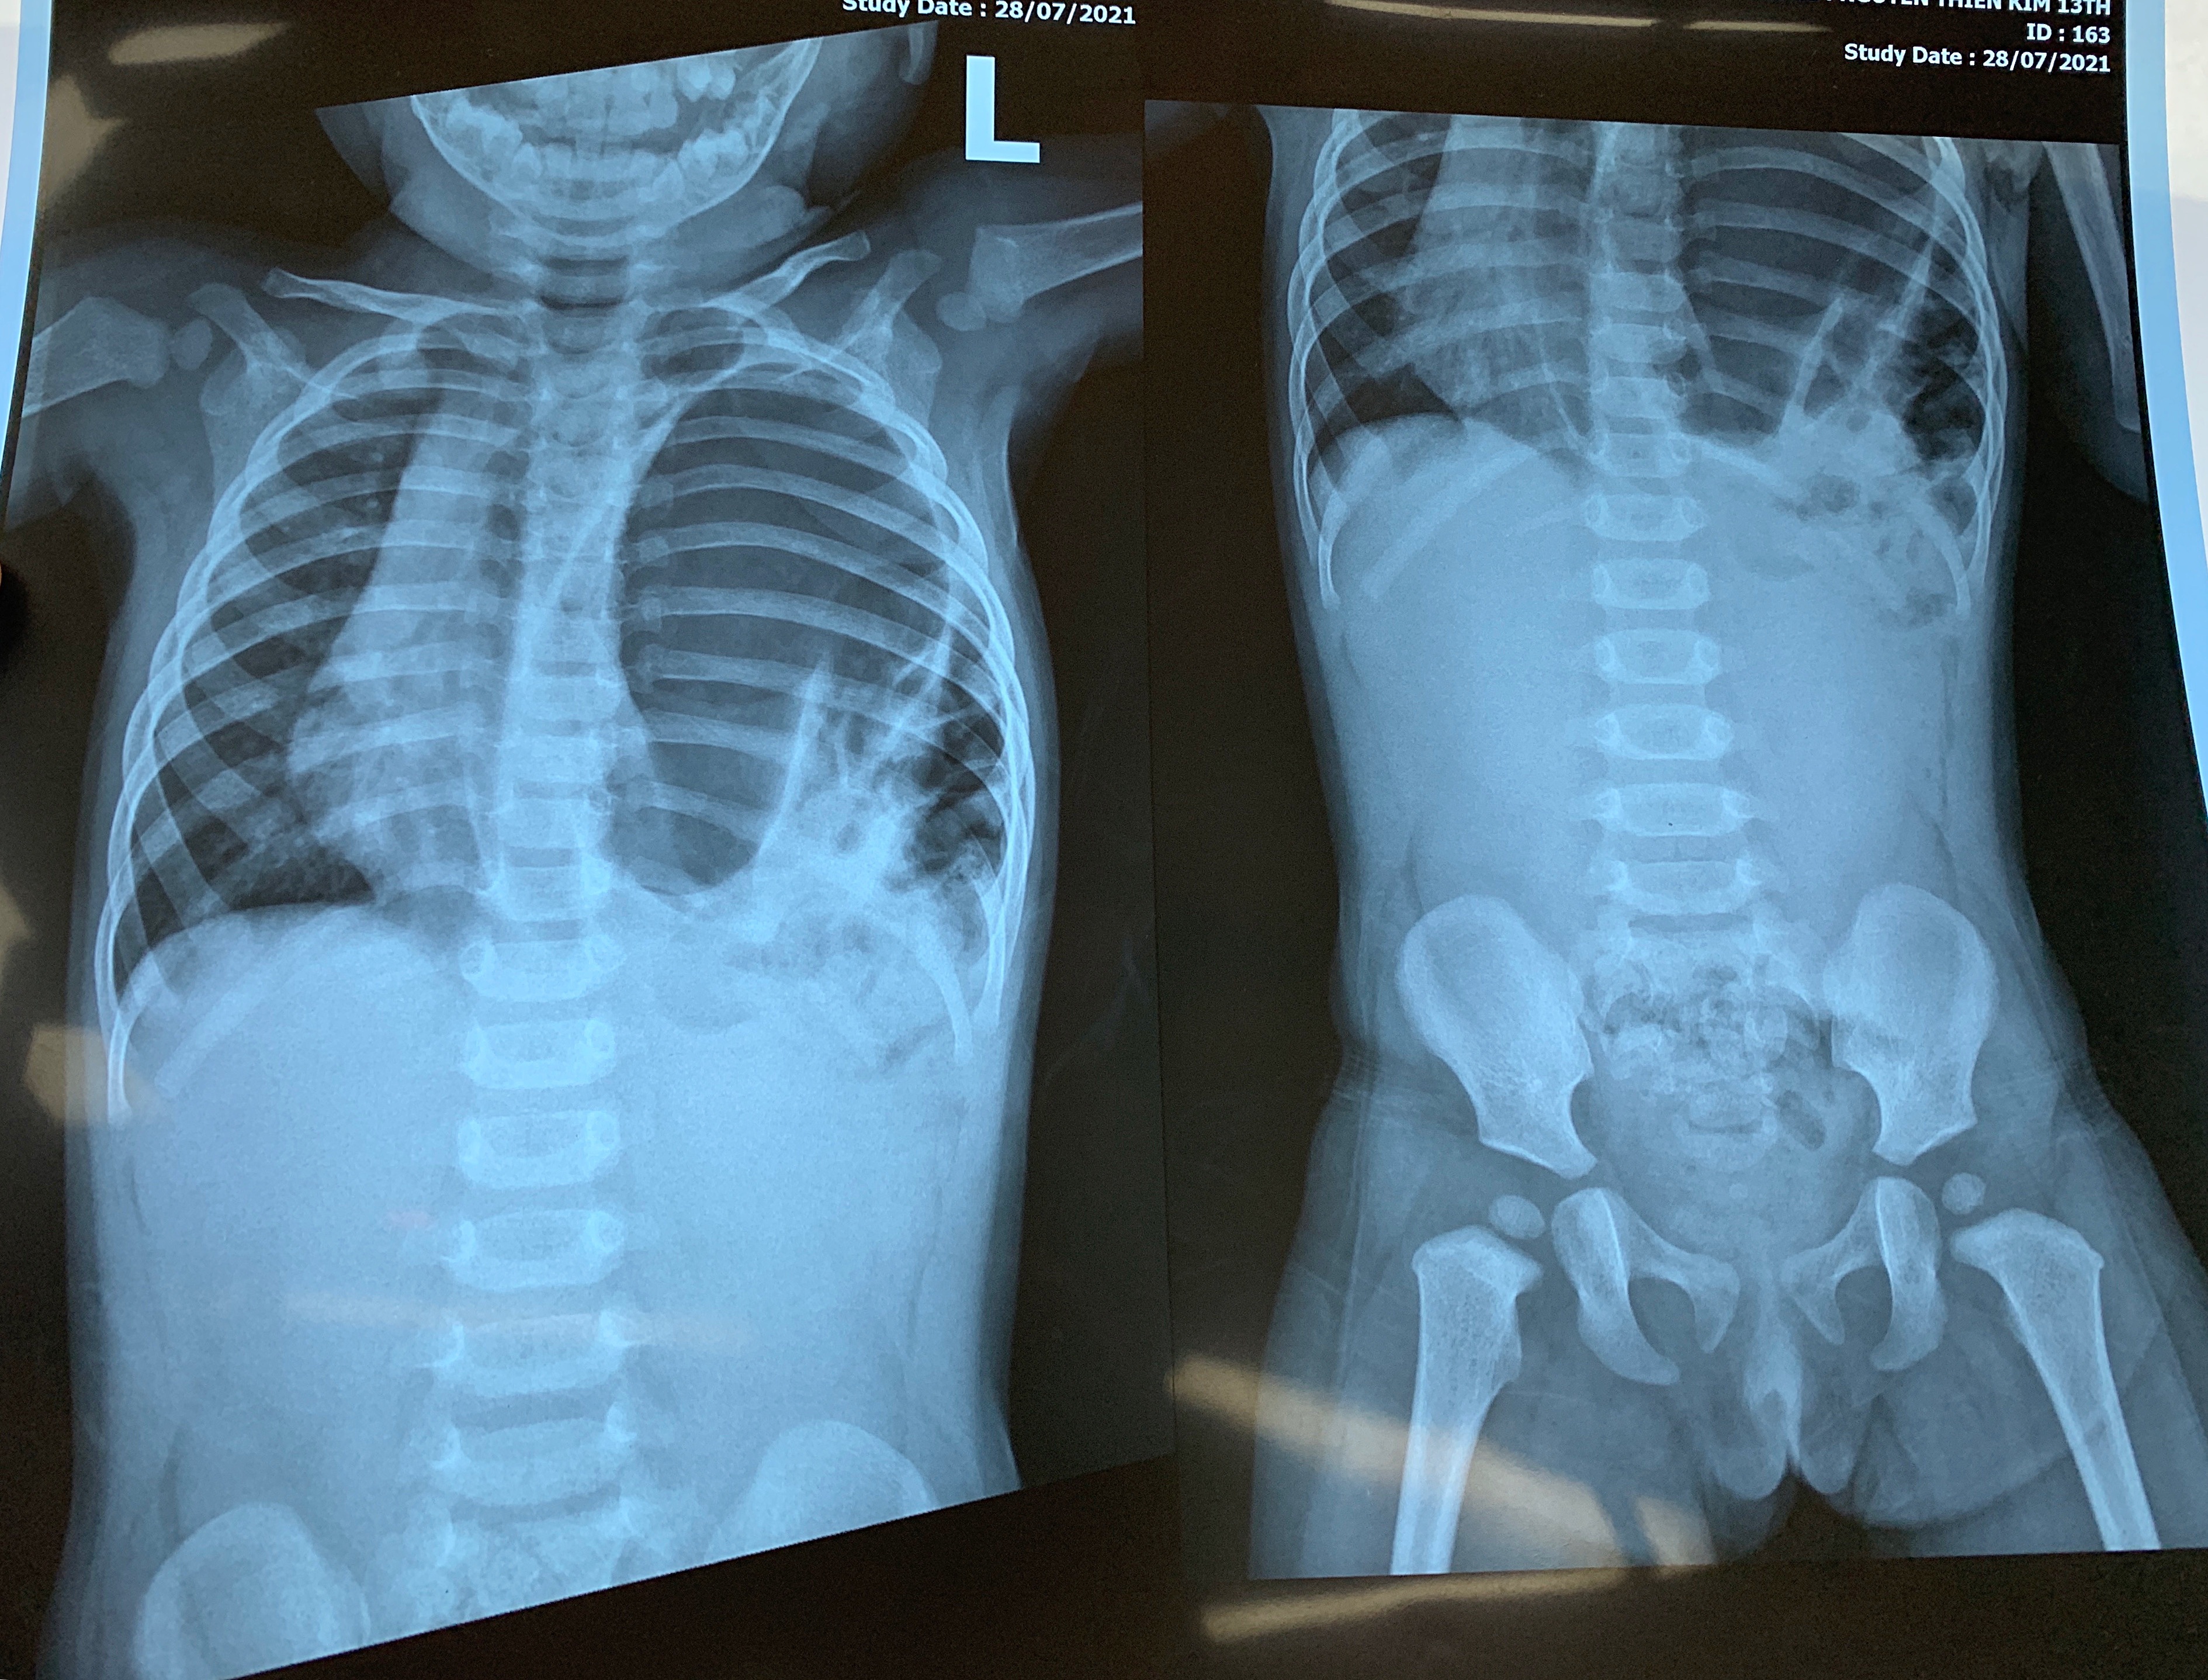

Hình ảnh X-quang thoát vị hoành trái của bệnh nhi. Ảnh: BVCC.

Sau khi có kết quả chụp X-quang, các bác sĩ chẩn đoán bé K. bị suy hô hấp rất nặng. Các tạng trong ổ bụng như dạ dày, ruột, lách đều chui qua lỗ thoát vị hoành bên trái lên thành ngực chèn ép, làm xẹp phổi trái và đẩy tim lệch nghiêng sang phải (nguy cơ xoắn cuống tim). Tình trạng này khiến K. có nguy cơ tử vong rất cao.